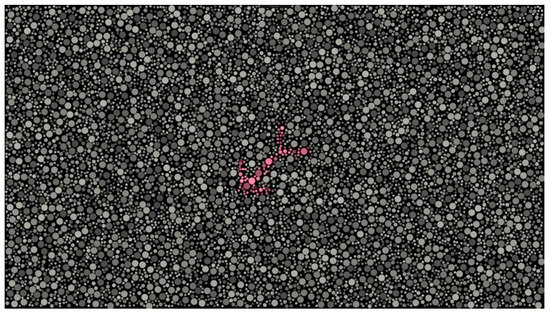

DIVE Color Test